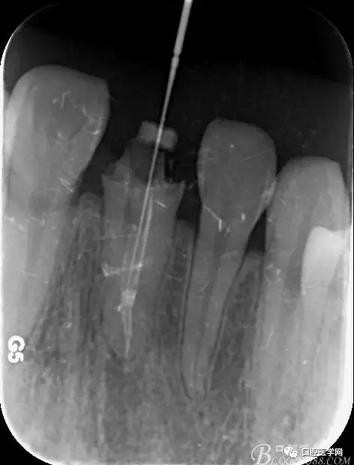

輔助檢查:X線見根尖區(qū)輕低密度影像,根尖1/3見根充物密實恰填,根管上2/3見折斷纖維樁,與根管密實。

術(shù)前X線片